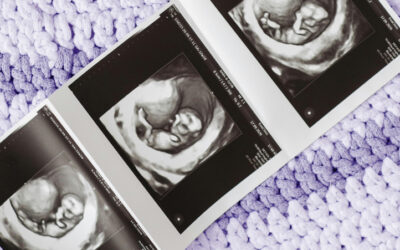

Face It . . . Abortion Kills!